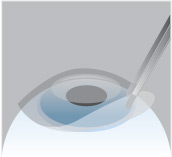

Step 4

A bandage-like soft contact lens is then placed on the cornea to help protect the eye as it heals.